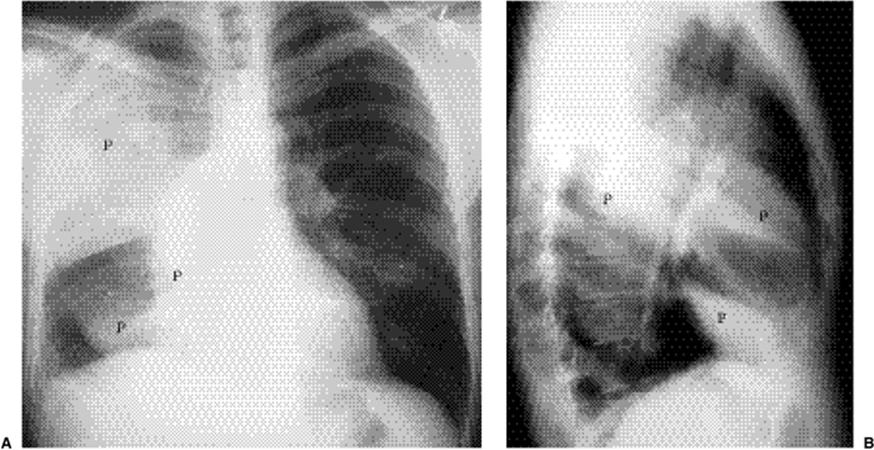

Focal opacity may be visible, especially when comparing one lung with the other on the frontal projection. On the lateral projection attention should be directed over the thoracic spine, the cardiac silhouette, and the retrosternal and retrocardiac regions, where faint opacity may otherwise escape detection (Figs. 5.1 and 5.2).

Figure 5.2 Opacity in pneumonia. (A) Posteroanterior and (B) lateral chest radiographs: vague retrocardiac abnormality (P) with corresponding increased opacity over the lower thoracic spine on the lateral view (arrows).